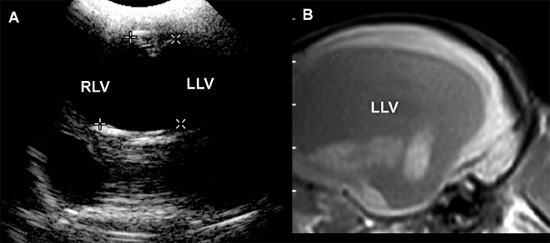

Figure 1.12. Incidental ventriculomegaly. Sonogram and magnetic resonance image (MRI) of the brain of a 10-year-old Maltese with severe but incidental ventriculomegaly. The ventriculomegaly was noted during spinal MR imaging performed to evaluate intervertebral disc herniation in the cervical region. The dog was not showing clinical evidence of brain abnormalities. A: Transverse sonogram showing massive ventriculomegaly involving the right and left lateral ventricles (RLV and LLV, respectively). B: Parasagittal MRI showing a severely dilated left lateral ventricle (LLV).

It may also be useful to evaluate the amount of brain tissue spared by the dilated ventricles. Animals with very little brain tissue commonly have severe neurological deficits, although that is not always true (Figure 1.12).

Several studies using ultrasonography or magnetic resonance imaging (MRI) have shown that the severity of clinical signs is not directly related to the degree of ventriculomegaly, and ventriculomegaly can be seen in neurologically normal dogs (De Haan et al. 1994; Vullo et al. 1997). A study using MRI to compare ventricular volume in Yorkshire terriers to that in German shepherds indicated that percentage of ventricle area to hemispheric area was significantly greater in the Yorkshire terriers, but the range of ventricle area for neurologically normal Yorkshire terriers overlapped that of neurologically abnormal Yorkshire terriers (Estave-Ratsch et al. 2001). Ventriculomegaly should not be equated with clinically significant hydrocephalus (Hudson et al. 1990; Spaulding and Sharp 1990; Ettinger and Feldman 2005). Breed differences and severity of clinical signs should be considered. Measurement of blood flow in the basilar artery might help to identify animals in which enlarged ventricles are significant or are likely to become clinically significant (Saito et al. 2003). In one study, RI at the basilar artery was higher in dogs with clinical hydrocephalus or other brain disease compared with normal dogs or dogs with asymptomatic hydrocephalus. Additionally, asymptomatic dogs with severe ventriculomegaly and high RI later developed clinical signs, although the use of high RI by itself did not identify asymptomatic dogs that were likely to become symptomatic (Saito et al. 2003).